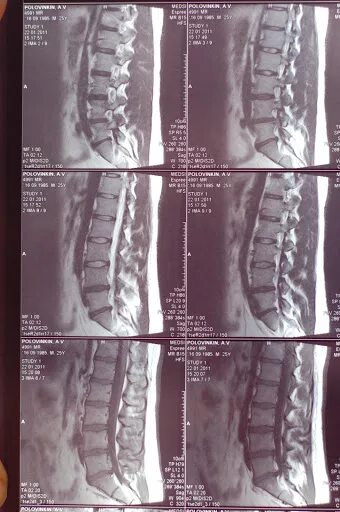

Лфк при грыже l5 s1